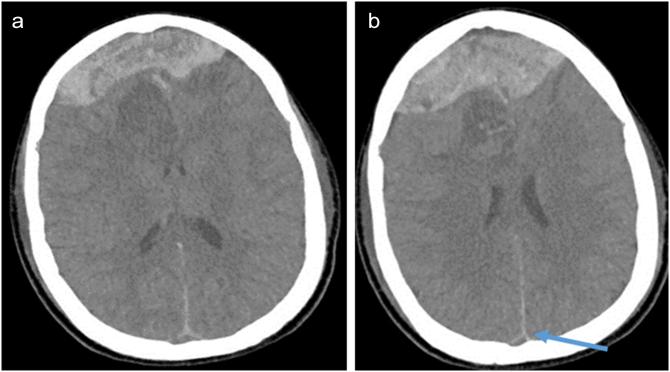

Massive spontaneous subdural hemorrhage mimicking dural venous thrombosis in a sickle cell adolescent, a rare case report.

We report a rare case of acute spontaneous subdural hemorrhage in an adolescent sickle cell patient of African descent.

我们报告了一例非洲裔青少年镰状细胞病患者急性自发性硬膜下出血的罕见病例。